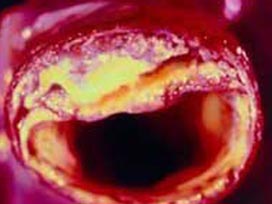

Atardamarlar üç boyutlu izlenebilecek